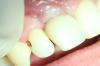

METT Опубликовано 26 апреля, 2013 Автор Поделиться Опубликовано 26 апреля, 2013 (изменено) 45-кариес 5 класс,кариес дистально,две небольшие изолированные полости,пломба дистально и щечно,полировка Изменено 26 апреля, 2013 пользователем METT Ссылка на комментарий